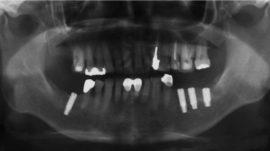

Sterowana regeneracja kości (GBR, Guided Bone Regeneration) wykorzystywana jest do odbudowy kości wyrostka zębodołowego w pożądanym wymiarze. Zabieg można wykonać podczas implantacji lub przed wprowadzeniem implantu, jako oddzielną procedurę. Uzyskuje się dzięki niemu poszerzenie lub podwyższenie wyrostka zębodołowego.

W implantologii regeneracji poddaje się kość wyrostka zębodołowego szczęki lub żuchwy, która uległa z różnych przyczyn zanikowi – jej niedostateczna ilość i jakość uniemożliwia wprowadzenie implantów. Po zakończeniu procesu sterowanej regeneracji, kość jest trwale zmieniona i często nie do odróżnienia od kości własnej.